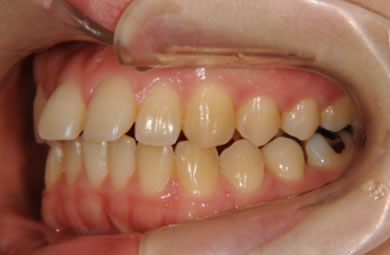

| 性別/年齢 | 女性 / 24歳 | ||||||||||||||||||||||||||||||||

| 主訴 | 矯正治療を希望し治療方針を相談する為、来院。 | ||||||||||||||||||||||||||||||||

| 治療方針 | 舌が横にはみでて、上下の歯が全く咬んでいない状態です。口元はきれいなので、歯は抜かずに歯列を少し横に広げて並べます。ゴムを使用したり、舌を訓練したりとても協力が必要な症例です。 | ||||||||||||||||||||||||||||||||

| 治療内容 | 唇側矯正(ホワイト)、保定装置 | ||||||||||||||||||||||||||||||||

| 総治療費 | 721,000円 | ||||||||||||||||||||||||||||||||

| 治療期間 | 9ヶ月 |